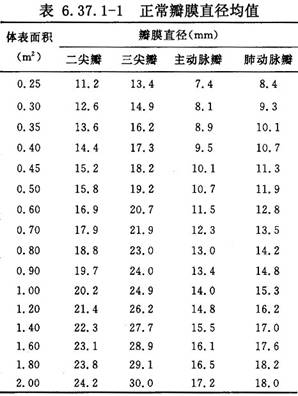

此方法优点在于既可缝缩后瓣环消除关闭不全,又尽可能保留瓣膜功能。加用垫片折叠,缝线不易撕脱,必要时用两个垫片褥式加固缝合。折叠后的二尖瓣口,成人为两指,10岁以下儿童一指到一指半。儿童二尖瓣环数值参考(表6.37.1-1)。